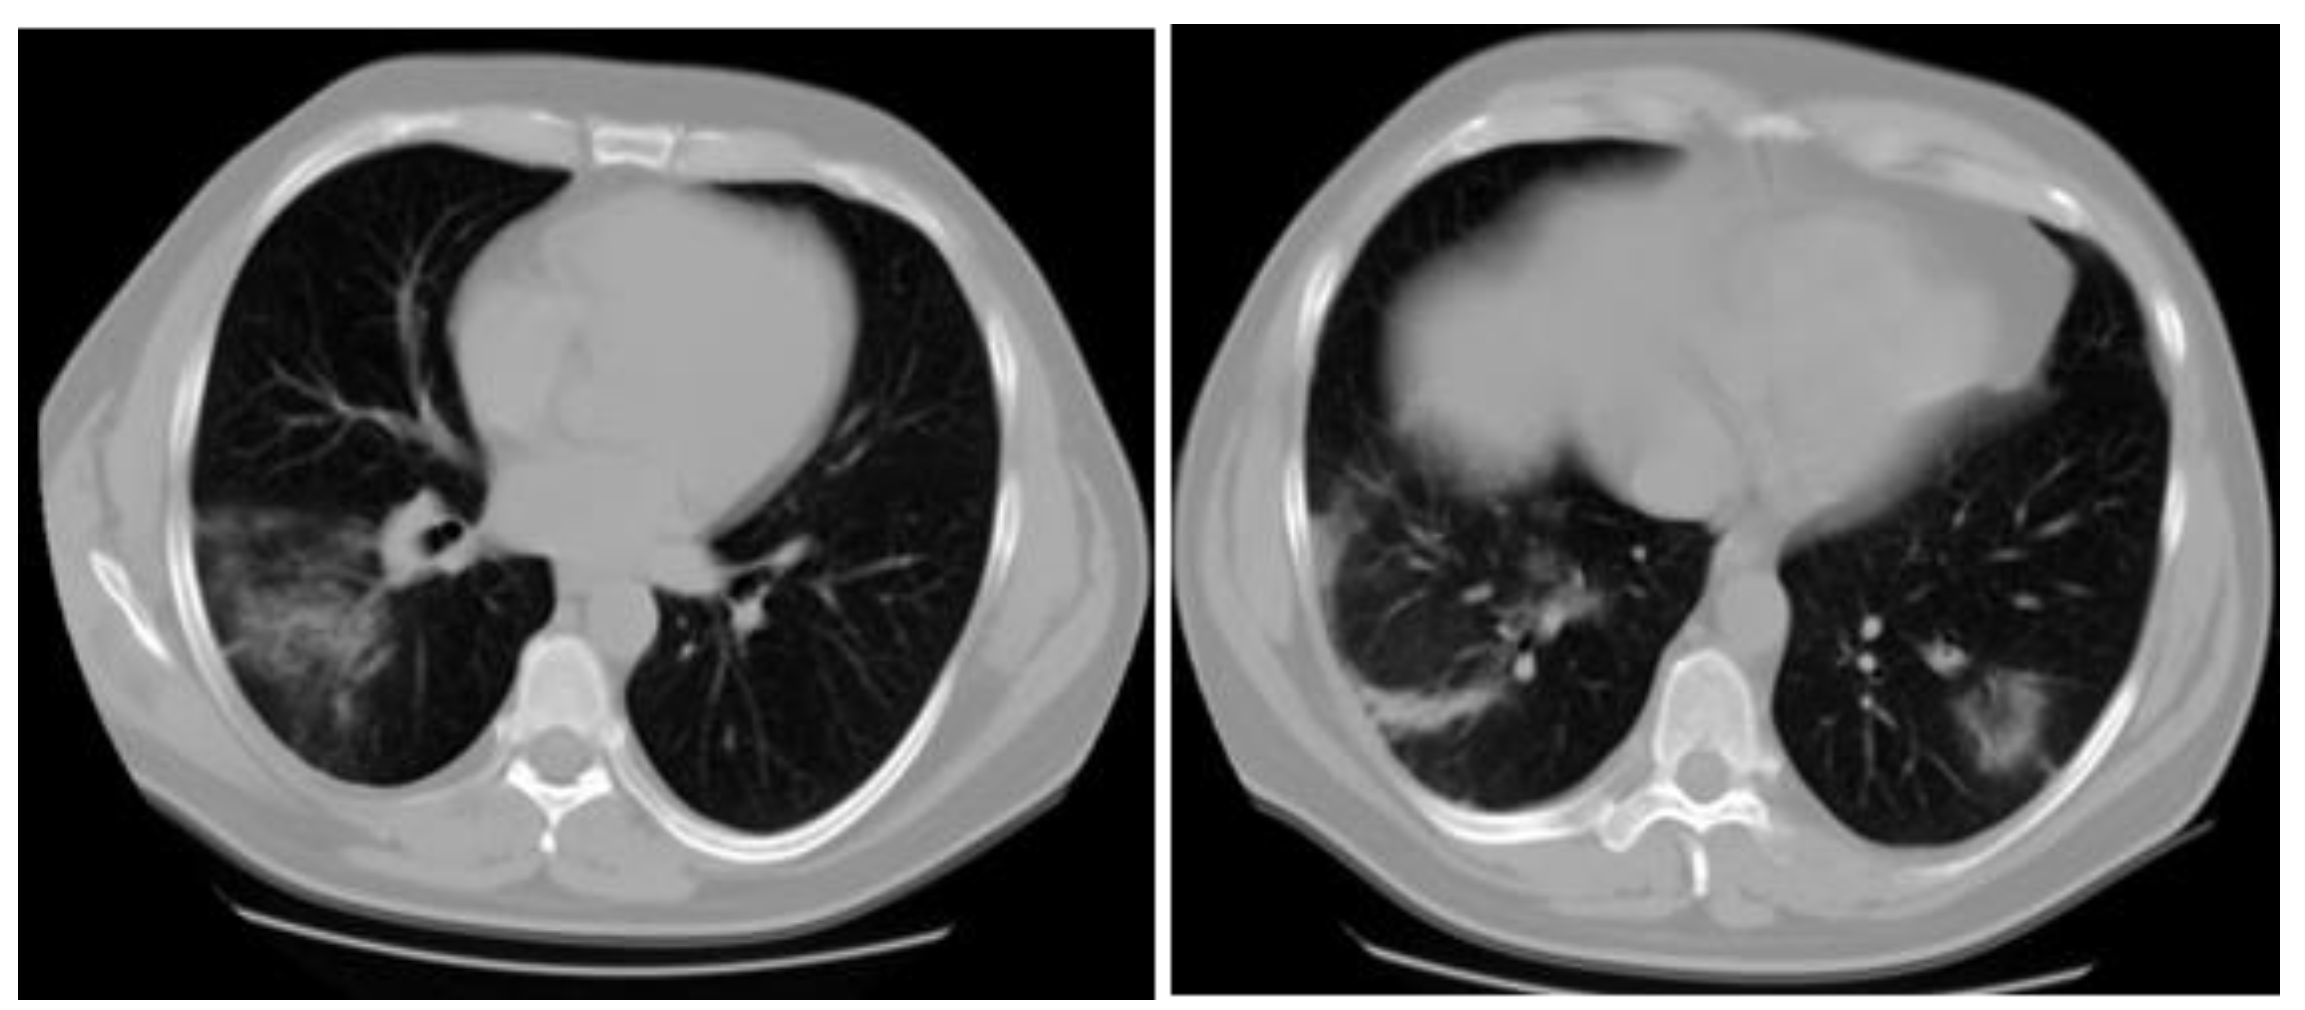

Case report